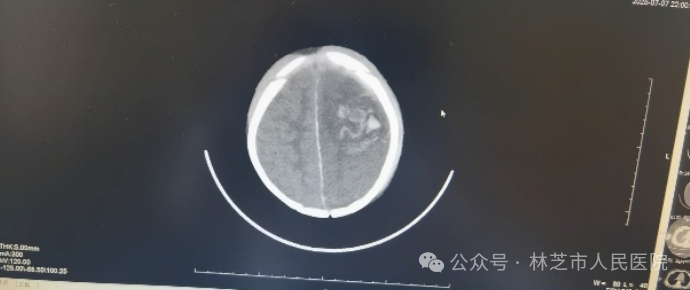

7月7日晚9时,还处于高原适应期的张春敏主任接到儿科值班医生的紧急电话:一名昏迷不醒、呼吸微弱的幼儿被送入医院,双侧瞳孔不等大,生命危在旦夕。尚未克服高原反应的张春敏主任立即电话中指导抢救,顶着高原缺氧的状态急速奔赴医院。查体发现患儿左侧枕部淤肿,凭借丰富经验,他迅速判断患儿存在严重颅脑创伤、颅内出血合并脑疝,当即汇报医院医务科启动绿色通道,连夜联系影像科,并同值班医生护送患儿完成急诊头颅CT检查,确诊为“左侧额颞顶叶脑挫伤、蛛网膜下腔出血、硬膜下/外出血、脑疝”。时间就是生命,张主任立即联系了同批援藏专家神经外科谢韬主任到场评估手术救治。

7月7日晚急诊头颅CT情况